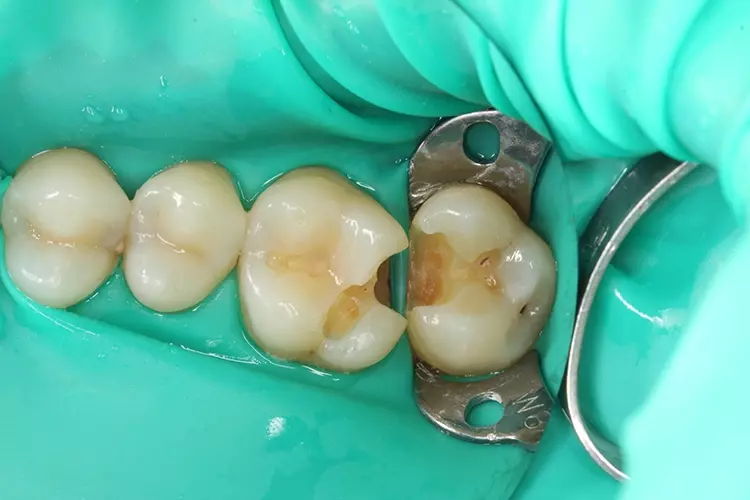

Für die Füllung an Zahn 26 wurde anschließend eine noch dünnere Stahl-Teilmatrize für Molaren angelegt (bombierte Teilmatrize Quickmat Deluxe, 0,025 x 6,4 mm, Polydentia), mit einem Keil zervikal abgedichtet und letztendlich noch ein Spannring (Palodent, Dentsply Sirona) eingesetzt (Abb. 8). Nach dem Einbringen von Flow- und Bulk-Fill-Inkrementen in der bewährten und bekannten Schichttechnik wurde die Teilmatrize entfernt. Diese ließ sich nur gegen hohen Abzugswiderstand entfernen, was mit einem starken Approximalkontakt korrespondierte (Abb. 9).

In der hier beschriebenen Falldokumentation wurde bei der relativ flachen Kavität an Zahn 27 zunächst nur die Randleiste aufgebaut und damit in eine Klasse-I-Kavität überführt (Abb. 5 und 6). Es folgte die Rekonstruktion der Okklusalfläche mit je einem Inkrement für den palatinalen und bukkalen Höckerabhang (Abb. 7). An Zahn 26 wurde wegen der schmalen, in mesiodistaler Richtung verlaufenden Kavität vorab keine primäre approximale Wand aufgebaut.

Stattdessen wurden, ausgehend vom Kavitätenboden, zuerst der distopalatinale Höckerabhang und die approximale Wand modelliert (Abb. 8). Auch hier wurde im Rahmen der Inkrementtechnik jeweils eine maximale freie Oberfläche angestrebt [5,7,8].